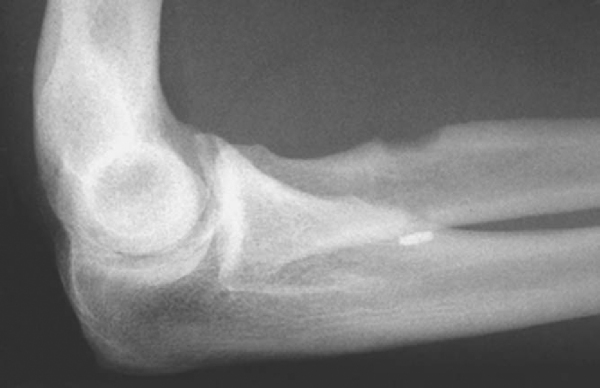

Although radiographs are typically normal, an anteroposterior, a lateral, and two oblique views are obtained. On occasion, avulsions of the tuberosity have been demonstrated in the acute setting. In the chronic setting, hypertrophic changes of the tuberosity may be noted.[14]